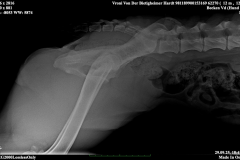

HD ZW: kW25/02 „69“ Größen-ZW: kW25/02 „101!